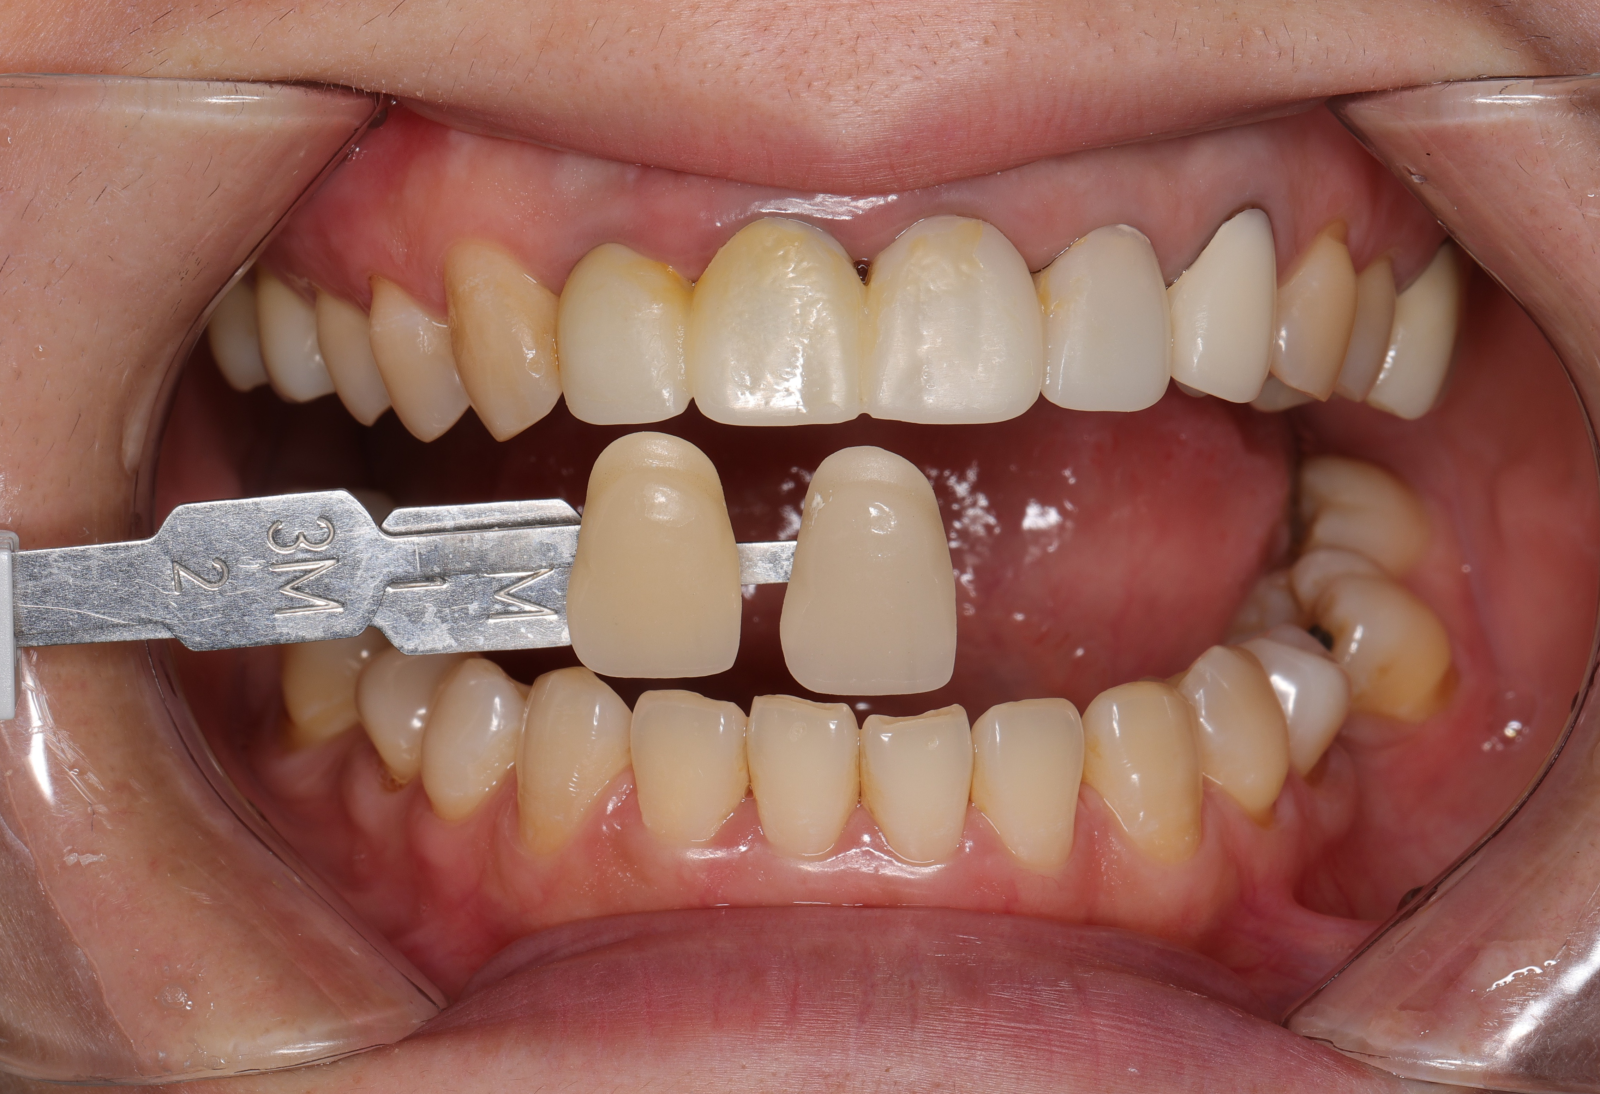

希望牙齒前牙區能一致變白,型態上也希望能調整得更自然,跟醫生討論之下決定把笑容區6顆牙齒都一起做前牙美學,用全瓷冠搭配美白貼片一起處理!

- 先把舊的假牙拆除後換成臨時假牙,期間先做冷光美白讓牙齒的基礎顏色變白,用保養型冷光美白,讓其他自然牙的部分可以白2~3個色階。一段時間讓顏色穩定後就可以當作正式全瓷冠的顏色參考。

-

經過數位微笑曲線設計,選擇自己喜歡的色階後就可以製作適合自己的美學全瓷牙囉!全瓷冠經過特殊處理呈現的通透感,讓牙齒白而自然透亮。